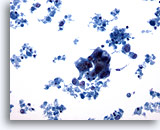

Figure 52

Breast FNA, Colloid (mucinous) carcinoma. Clusters of small cells and some single cells are shown in a background of mucin. It is preferable to report such cases as ductal carcinoma showing mucinous differentiation rather than colloid or mucinous carcinoma as the diagnosis is dependent upon the whole tumor showing mucin production. 40x

Figure 52

Breast FNA, Colloid (mucinous) carcinoma.

Clusters of small cells and some single cells are shown in a background of mucin. It is preferable to report such cases as ductal carcinoma showing mucinous differentiation rather than colloid or mucinous carcinoma as the diagnosis is dependent upon the whole tumor showing mucin production.

40x